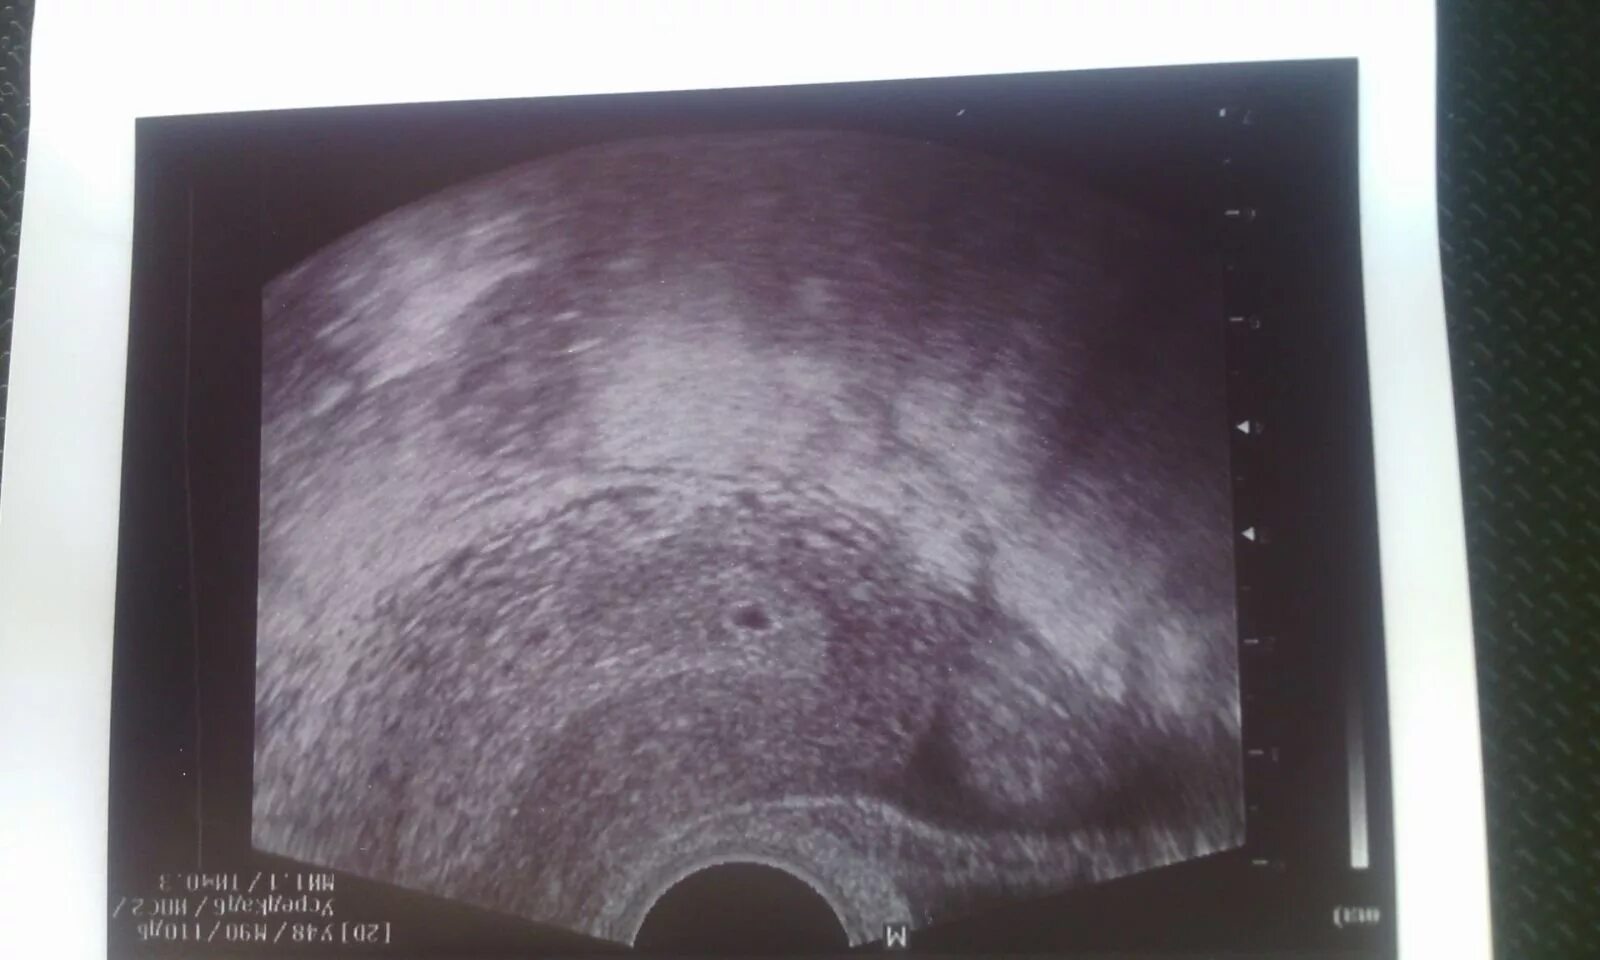

Анэмбриония – пустое плодное яйцо. плодное яйцо 7 мм желточный мешок 6 мм. снимок узи пустого плодного яйца.

Анэмбриония – пустое плодное яйцо. неразвивающаяся беременность узи. пустое плодное яйцо на узи. узи 8 недель беременности анэмбриония.

Неразвивающаяся беременность узи. неразвивающаяся беременность анэмбриония. что такое анэмбриония плодного яйца. узи признаки анэмбрионии.

Пустое плодное яйцо на узи. анэмбриония – пустое плодное яйцо. плодное яйцо на узи на ранних сроках 2 недели. ложное плодное яйцо на узи.

Плодное яйцо 10 мм анэмбриония.